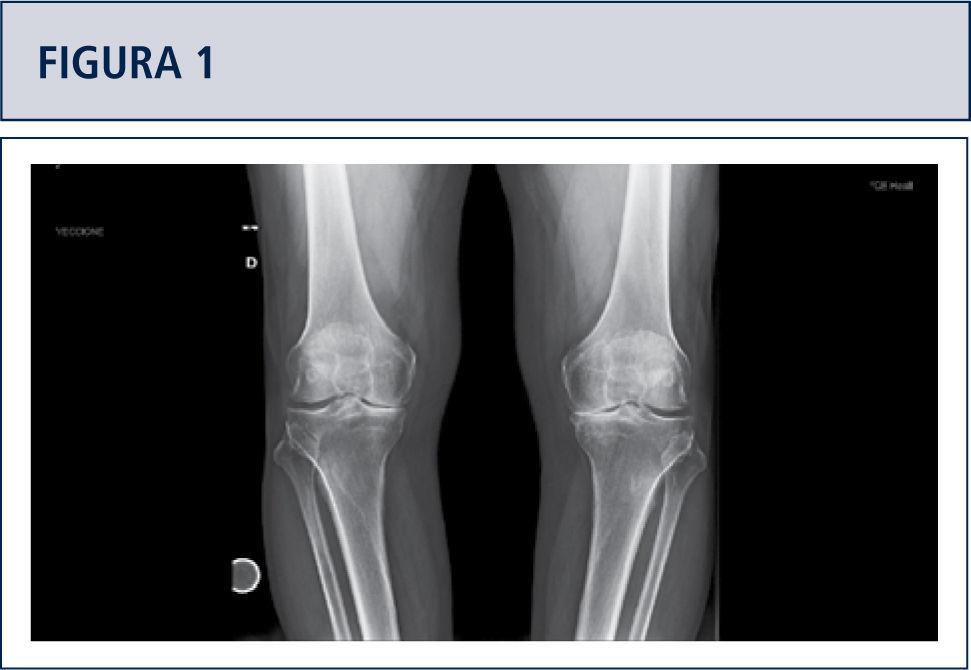

Theo hướng dẫn của Bộ Y tế, X-quang là phương tiện đầu tay giúp xác định thoái hóa với các dấu hiệu đặc trưng như hẹp khe khớp, gai xương và đặc xương dưới sụn. MRI không phải lúc nào cũng cần thiết, chỉ chỉ định khi nghi ngờ tổn thương sụn chêm hoặc dây chằng.